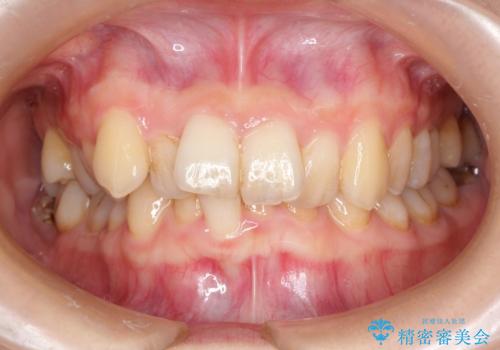

初診時の歯並びの状態としては、上下ともに前歯部の中等度のがたつきがあり、下の前歯は本来生えるはずの歯が2本生まれつき欠損している状態でした。

また、上顎の歯は虫歯で歯冠が崩壊してしまって保存不可能な歯がありました。